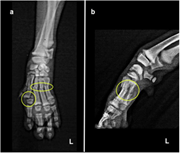

The animal was admitted for further diagnostic investigations and pain management. Emergency pain management included the administration of carprofen (Rimadyl; Zoetis) 4mg/kg as a single subcutaneous injection. The animal was prepared for general anaesthesia in order to acquire radiographs of the affected limp. Anaesthetic premedication included the administration of xylazine (Rompun; Bayer) 1mg/kg intramuscular injection in conjunction with atropine (Atropine Sulfate; Bradex) 0.01mg/kg intramuscular injection. Induction was achieved with propofol (PropoFlo; Zoetis) 2mg/kg administered intravenously in a bolus rate. Anaesthesia was maintained with a mixture of isoflurane (IsoFlo; Abbott) 1.5% with 20% oxygen in a constant inhalation rate administered via a cuffed endotracheal tube throughout. One lateral (LT) and one dorsopalmar (DP) radiograph of the carpo-metacarpal region were acquired, incorporating the distal antebrachium (Photo 1). Radiographs revealed the presence of single transverse shaft fractures of the third (CIII), fourth (CIV) and fifth (CV) carpal bones, located at the proximal second fourth (2/4) of the carpal body in all carpals. A moderate caudo-lateral dislocation of the distal fracture fragments was present in all three carpals. There was also a symphysiolysis of the distal symphysis of the second (CII) carpal bone right above the dorsal sesamoid, with lateral dislocation. Nothing abnormal was detected on the distal antebrachium, the carpus and the phalanges. These findings were deemed consistent with the presence of pain, swelling, abnormal gait, crepitus and valgus and would have resulted directly from an acute forelimb injury as also described by the animal’s history.3‒5

Photo 1 Dorsopaimar (a) and Lateral (b) radiograph of the metacarpais showing the fractures in the yellow circles. Notice the slight valgus of the forelimb evident on the dorsopalmar projection.